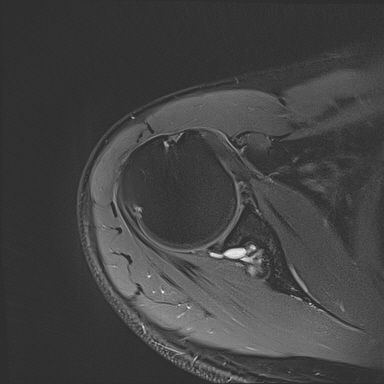

어깨 mri 좀 봐주세요 물혹있다고 하는데 수술해야 하나요?

하도 안 나아서 우측 견관절도 mri 촬영을 했는데 물혹이 있네요